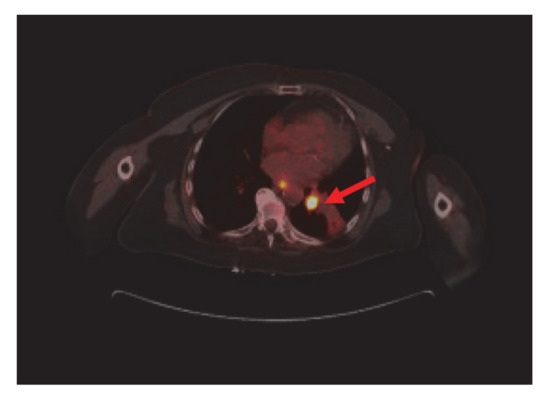

Four months into the treatment, the patient had a repeat CT scan done, which showed marked regression of the left lower lobe bronchial tumor (Figure 4) and re-expansion of the left lower lobe. The patient had been responding well to dabrafenib and trametinib. She continued with both agents with minimal side effects.

Figure 4.

Significant regression of the left lower lobe bronchial tumor (red arrow) and re-expansion of left lower love.